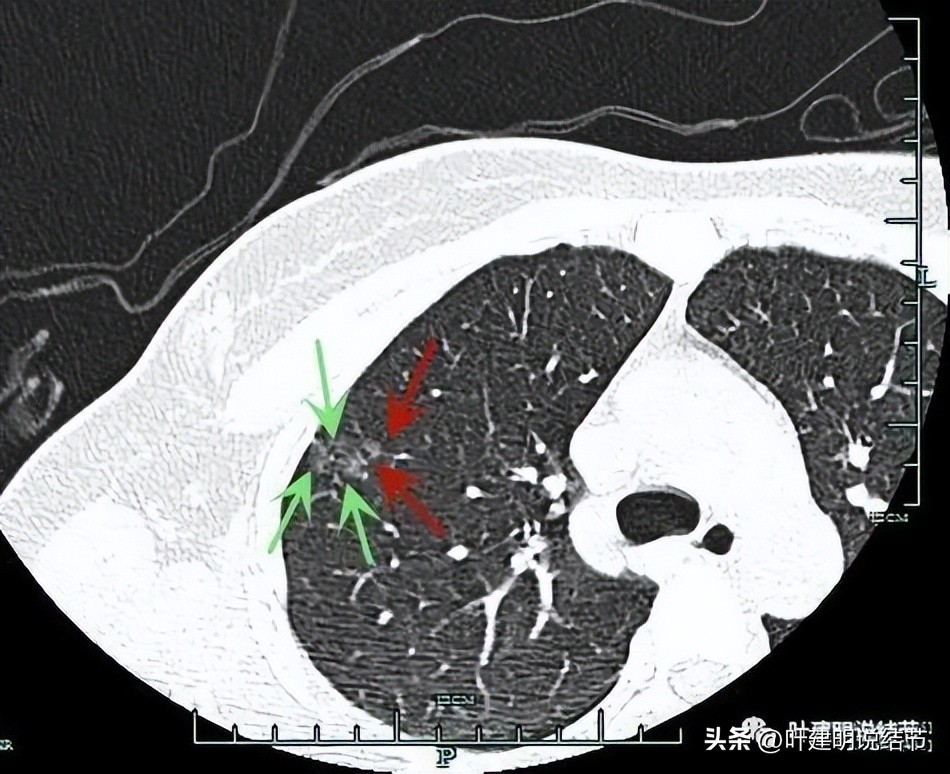

非薄层图像:

病灶1:右上叶淡磨玻璃结节,边缘较糊,似有微小血管走向病灶。

病灶2:右上叶混合磨玻璃结节,边缘毛糙,中间有空泡征,邻近有微小血管走向病灶。

病灶3:右下叶近叶裂处微小磨玻璃结节,偏长条状,有微血管进入。